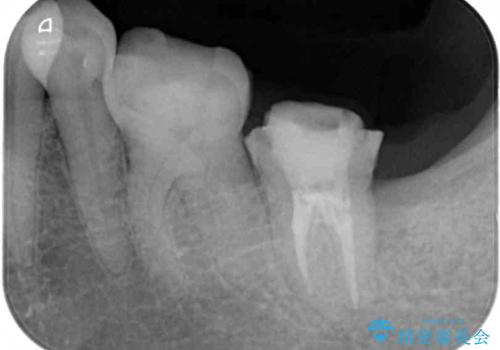

- かかりつけ医にて、歯の高さが不足しているためセラミッククラウンの装着はできないと言われたとのことで来院された患者様です。

診察したところ、確かに歯の高さは不足していましたが、土台の立て直しや歯の削り方を調整することでオールセラミッククラウンでも補綴可能と思われました。

ただし、クラウンの厚みは極力薄くした方が維持力が増すため、高強度のフルジルコニアクラウンにて補綴治療することとしました。